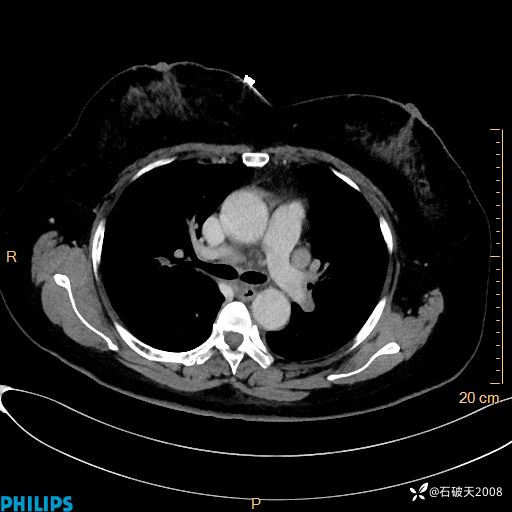

肺结节病?纵膈型肺癌?淋巴瘤?有点意思,欢迎围观

女 52岁 主 诉:咳嗽10余天,咳痰2天。

纵隔窗